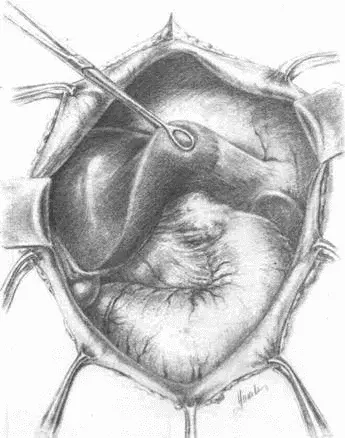

Рис. 71.Тотальная гастрэктомия. Треугольная связка левой доли печени

Рис. 72.Пересечение венечной связки при мобилизации левой доли

Рис. 73.Обкалывание нижней диафрагмальной вены

Рис. 74.Рассечение диафрагмы между двумя лигатурами

Рис. 75.Сагитальная диафрагмотомия. Мобилизован пищевод